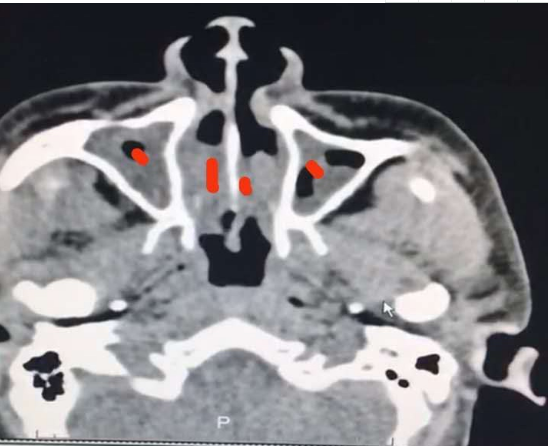

期间患者多次诉吸鼻后有黄色分泌物,遂复查鼻部CT示鼻腔内肿物(图1),鼻内窥镜活检病理报告示结外NK/淋巴瘤

图1